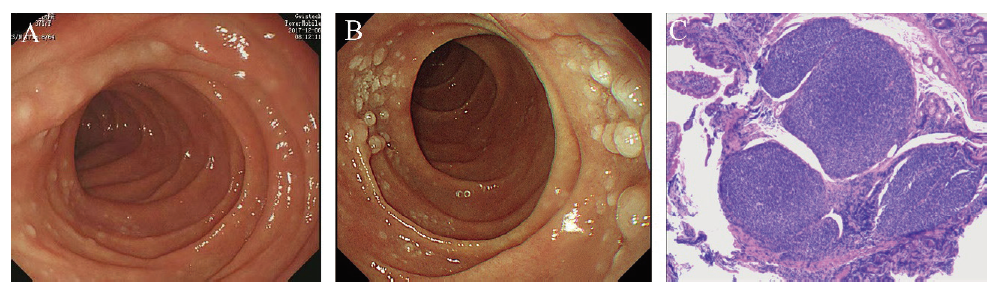

病例2 患者男,62岁,2022年1月12日因“健康体检”就诊于本院,患者无任何临床症状,体格检查无特殊。既往史:有高血压病史30年余,否认糖尿病、淋巴瘤等病史。实验室检查未见明显异常。胃镜示十二指肠未见黏膜病变(图2A);结肠镜示横结肠见数枚大小约0.3 cm×0.2 cm息肉样增生(图2B);乙状结肠见1枚大小约1.5 cm×1.5 cm黏膜下隆起,有蒂,表面光滑,色红;结肠上述2个病灶区予以组织活检。活检病理结果:(横结肠)息肉伴淋巴组织增生活跃(图2C);(乙状结肠)管状腺瘤伴低级别上皮内瘤变。横结肠活检组织免疫组化表型:肿瘤组织CD20(+),Bcl-2(+),Bcl-6(+),Pax-5(+),CD10(+),CD21(FDC+),CD79a(+),CD3(-),CD5(-),Ki-67(+,约10%),Cyclin D1(-),LMO2(+);初步诊断为D-FL。病理切片经多家上级医院会诊,诊断结果一致,确诊为D-FL(1级)。患者因无明显临床症状拒绝进一步治疗,遂建议患者观察随访。电话随访1年,患者未行任何药物治疗,病情无进展。

图2 病例2 D-FL患者胃肠镜及病理图片

注:A为胃镜下十二指肠降部黏膜表现;B为结肠镜下横结肠黏膜表现;C为横结肠黏膜病理结果(HE染色,40)。